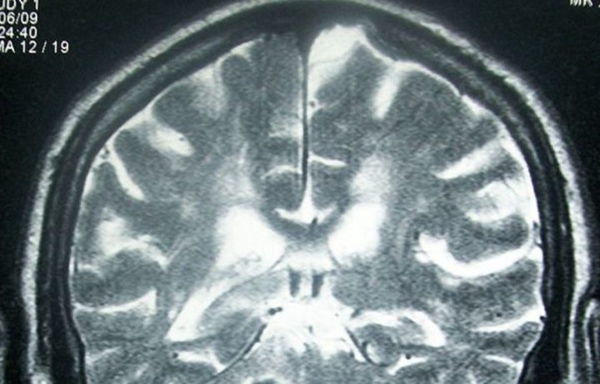

【天维网援引RNZ消息 Phoebe编译】一名16岁新西兰少女因放射科医生在核磁共振检查中漏诊了脑瘤病变的早期信息而遭受病痛折磨,最终离开了这个世界。

2014年8月,少女在医院接受了脑部核磁共振检查后被医生告知,一切正常。但8个月后,少女因剧烈的头痛和脚步不稳而入院。

医院在对她进行了检查后发现,少女脑部复发了恶性肿瘤。而这在2014年的脑部扫描中就已经初现端倪,当时为她做检查的放射科医生却因为疏忽没有发现。